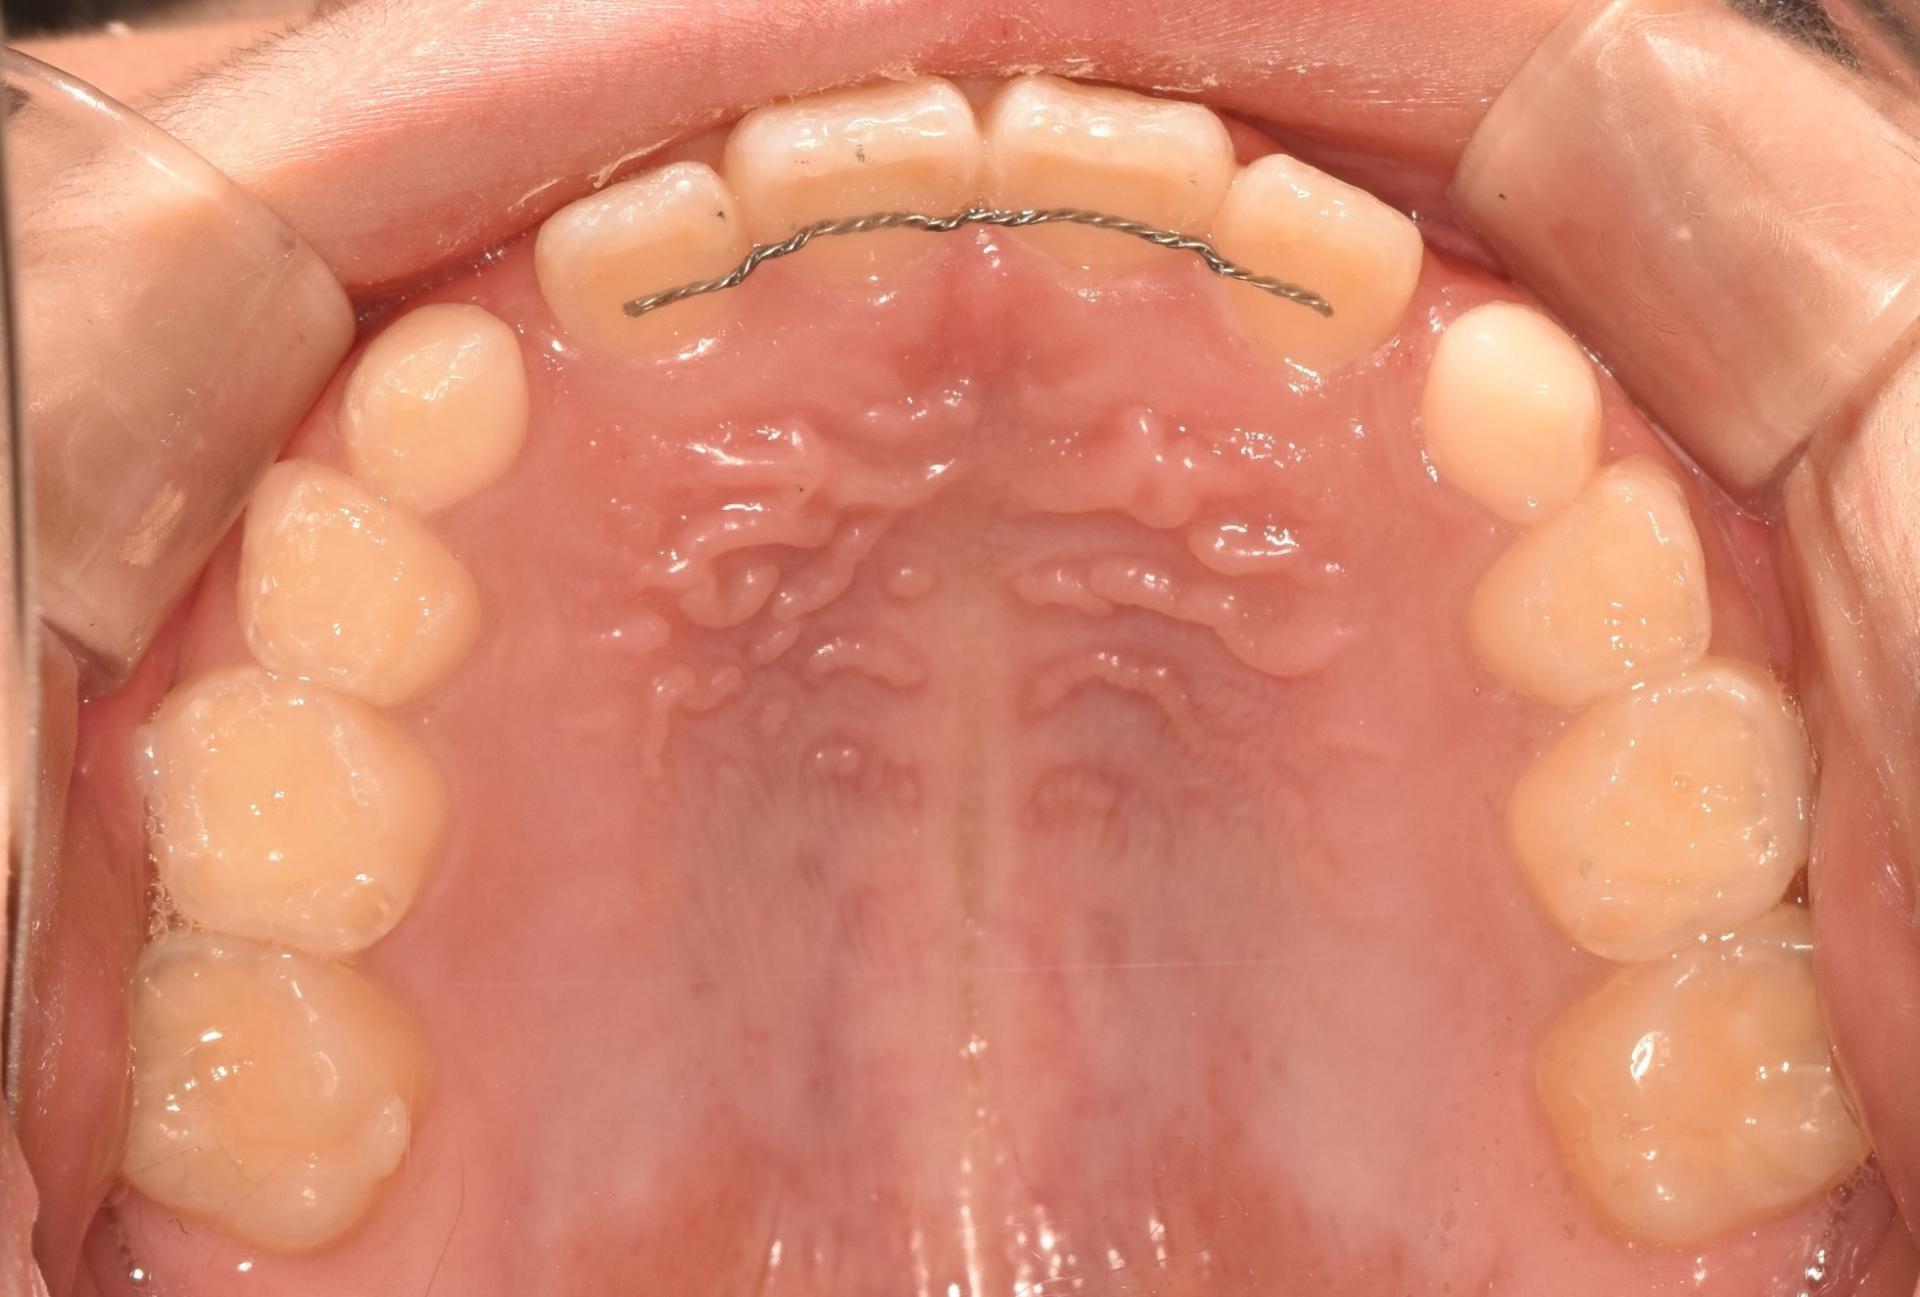

교정 진행중, 투명교정장치를 착용한 모습입니다. 치아위로 철사가 지나가지 않으니, 교정하는 것이 남들 눈에 띄지 않게, 편하게 뺏다 꼈다 하고, 철사 찔림이 발생하지 않으며 통증없이 치료를 진행할 수 있다는 장점이 있어 많은 어린이들이 선호하는 치료입니다!

1년의 교정치료 기간 끝에 뻐드러진 치아도 안으로 예쁘게 넣었고 부딪히는 치아 없이 배열도 완료 되었습니다. 더불어 덧니되지 않도록 앞으로 나올 송곳니의 자리까지 마련했답니다.